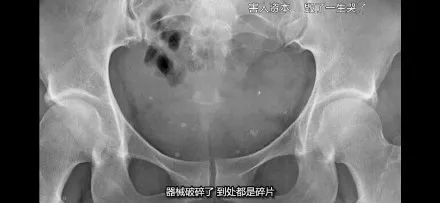

國外還有一個案例,是塑料的節育環在體內碎裂了,整個子宮都是節育環的碎片。

這場面,只是看着,我都小腹一緊……